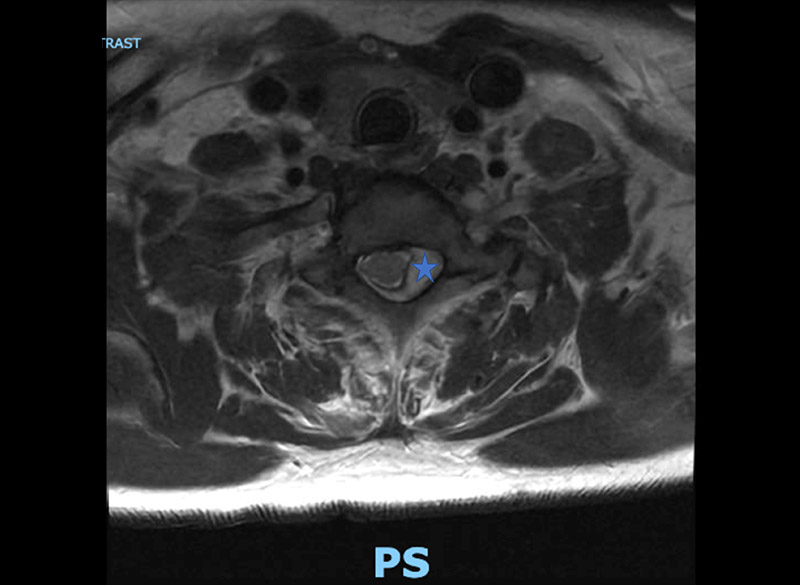

preop axial mri

Preop axial MRI at C7-T1, showing infection, marked by the star, pushing spinal cord to the right and causing spinal cord compression.